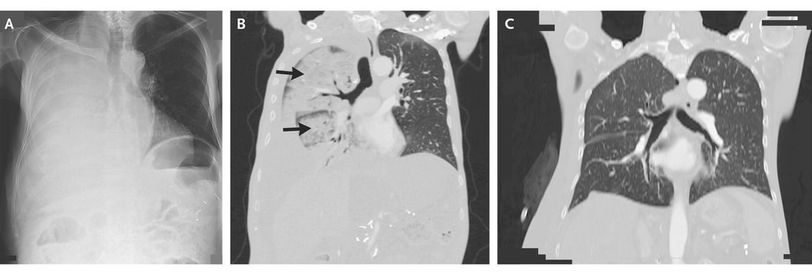

A 67-year-old-man with advanced alcoholic cirrhosis presented with progressive dyspnea. Chest radiography showed findings suggestive of a large right pleural effusion (Panel A). Since hepatic hydrothorax was suspected, thoracentesis was performed, resulting in the aspiration of 1500 ml of transudative fluid. Four hours later, the patient started coughing and had tachypnea and tachycardia, with right lung crackles heard on physical examination. The oxygen saturation was 82% while he was breathing ambient air. Computed tomography (CT) of the chest showed diffuse areas of consolidation and ground-glass opacity in the right lung (Panel B, arrows), suggestive of reexpansion pulmonary edema. After the patient received diuretics and high-flow oxygen through a reservoir mask, there was progressive improvement in his condition. After 4 days, a complete resolution of radiologic findings was seen on CT (Panel C). Reexpansion pulmonary edema can be a complication of thoracentesis. Treatment is largely supportive. Risk factors for this condition include a young age, a long duration of lung collapse, and rapid reexpansion.